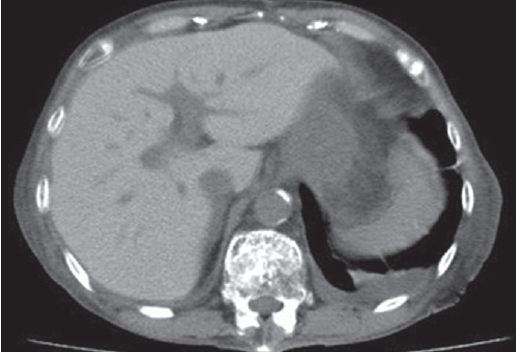

Abdominal plain computed tomography (CT) revealed an increased liver density (Fig. 1). These disorders were determined to be attributable to an overdose of amiodarone, and the drug was discontinued. Thyroid hormone replacement relieved her dementia; the dosage of thyroid hormone preparations was decreased over time and eventually discontinued. Moreover, the liver dysfunction gradually resolved. An abdominal plain CT scan performed 1 year later revealed a decrease in the high liver density (Fig. 2). During this period, no recurrence of paroxysmal atrial fibrillation was detected.

Figure 2.

Abdominal plain computed tomography scan performed 1 year later. The high liver density had decreased.